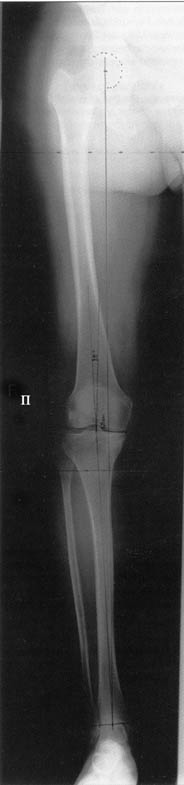

AC> Обратилась дама 25 лет. Вынуждена ходить в брюках из-за genu varum,

AC> что побудило обратиться за коррекцией.

Сейчас это модно (в смысле косметическая коррекция)... Хотя, судя по фото - в данном случае енто вполне оправдано...

Судя по снимку у девушки имеется внутренняя установка надколенников...

Как у нее с торсионным статусом? Бедро? Голень? КТ? Торсиометры? А то, куда будут

смотреть надколенники после вашей коррекции - тоже существенный

косметический момент. Или не так?